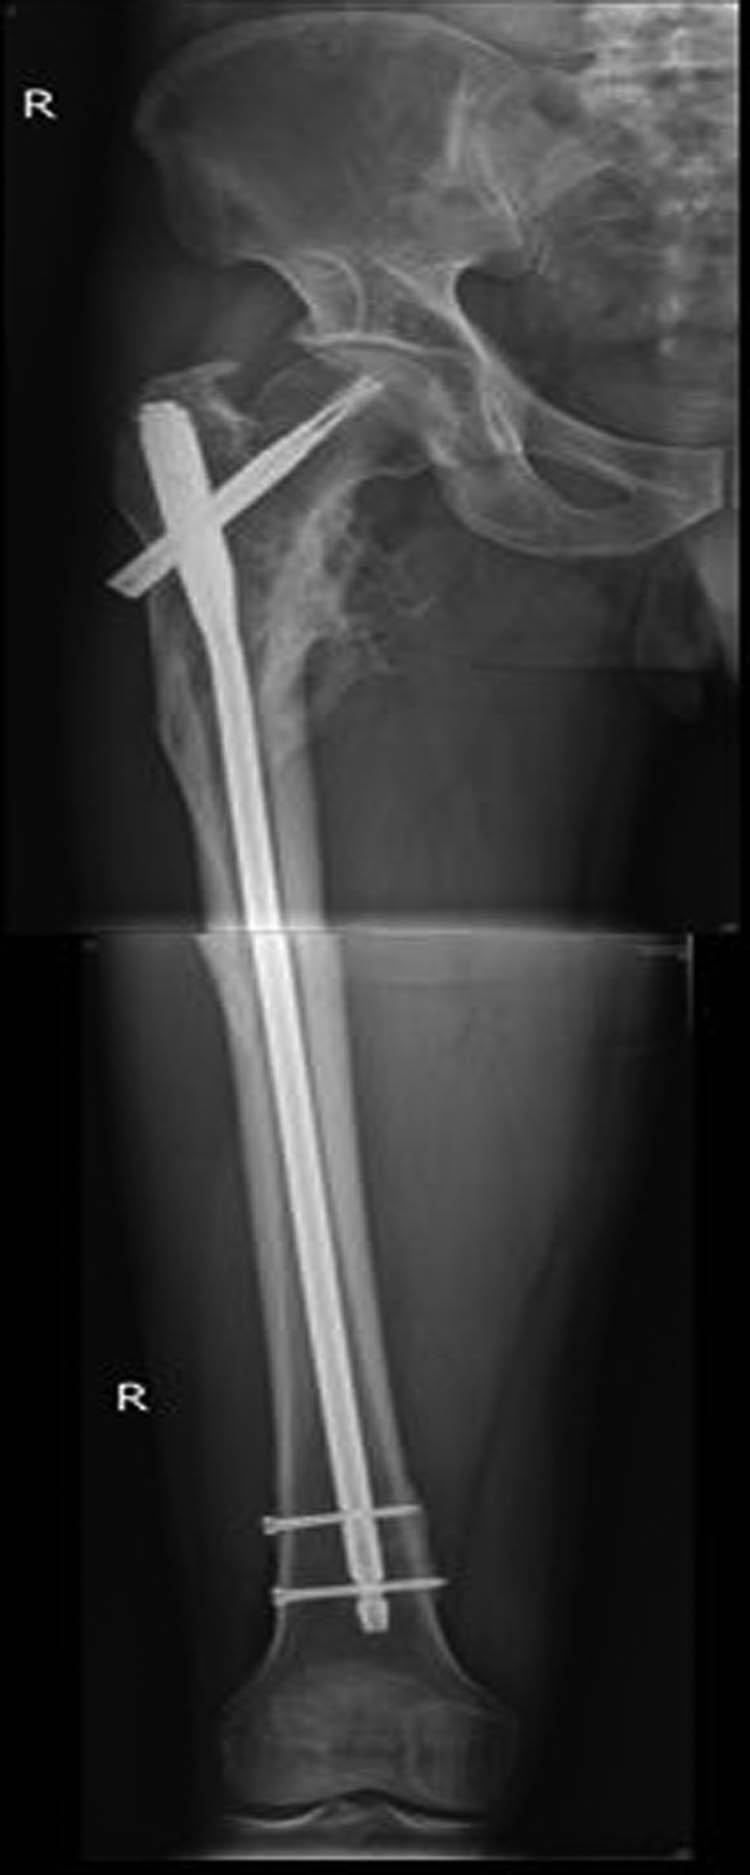

External fixation via the AIIS and distal femur was performed by a single surgeon under general anesthesia without regional nerve blockade during emergency surgery. External fixators derived from AO (Synthes, Ltd., Paoli, PA), Trauson (Trauson, Ltd., Changzhou), and Carefix (Carefix, Ltd., Shanghai) were used. Patients were placed in a supine position on the operating table. A C-arm was used to locate the points of the AIIS, and a minimal incision of 1–2 cm in length was made. The deep fascia of the pelvis and femur were incised. Proximally, the lateral femoral cutaneous nerve was protected by a surgical hook. One pin (diameter 6.0 mm, length 180 mm, thread length 60 mm) was placed at the AIIS on the same side as the PFF. Distally, two crossing pins (diameter 6.0 mm, length 180 mm, thread length 60 mm) were placed at the distal femur through two minimal incisions. High-strength and fully transparent carbon fiber rods (diameter 8 mm, length 400 mm) were fixed, manipulative reduction was performed along the strength line under the C-arm, and the clamps were tightened. The incisions were then sutured. A typical case is presented in Figures 2–5.

Patient with femoral intertrochanteric fracture accepted intramedullary nailing and the fracture eventually healed.